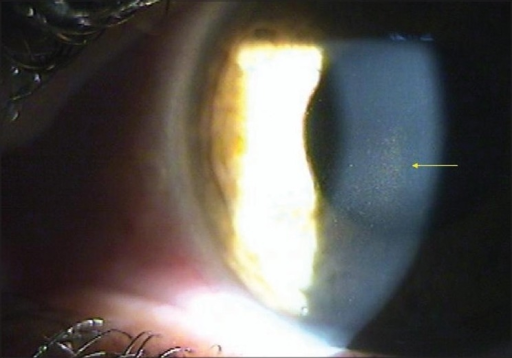

- Krukenberg spindle: 각막 내피면에 수직 방추형 색소 침착 — 가장 특징적

- Krukenberg spindle ⭐⭐⭐: 각막 내피 수직 색소 침착